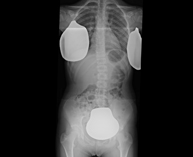

Estudi que usa els raigs X a través de la qual s'obtenen imatges del maluc i permet descartar luxacions. - RX Seriada òssia

Estudi que usa els raigs X a diferents parts del cos (crani, columna, costelles, pelvis, húmers i fèmurs) per descartar que existeixen lesions en aquests ossos. Indicacions: estudi del mieloma múltiple, gammapaties monoclonals, metàstasi. - RX Sacroilíaques

Estudi que utilitza els raigs X per obtenir una imatge dels ossos de maluc i descartar luxacions. - Cistografia